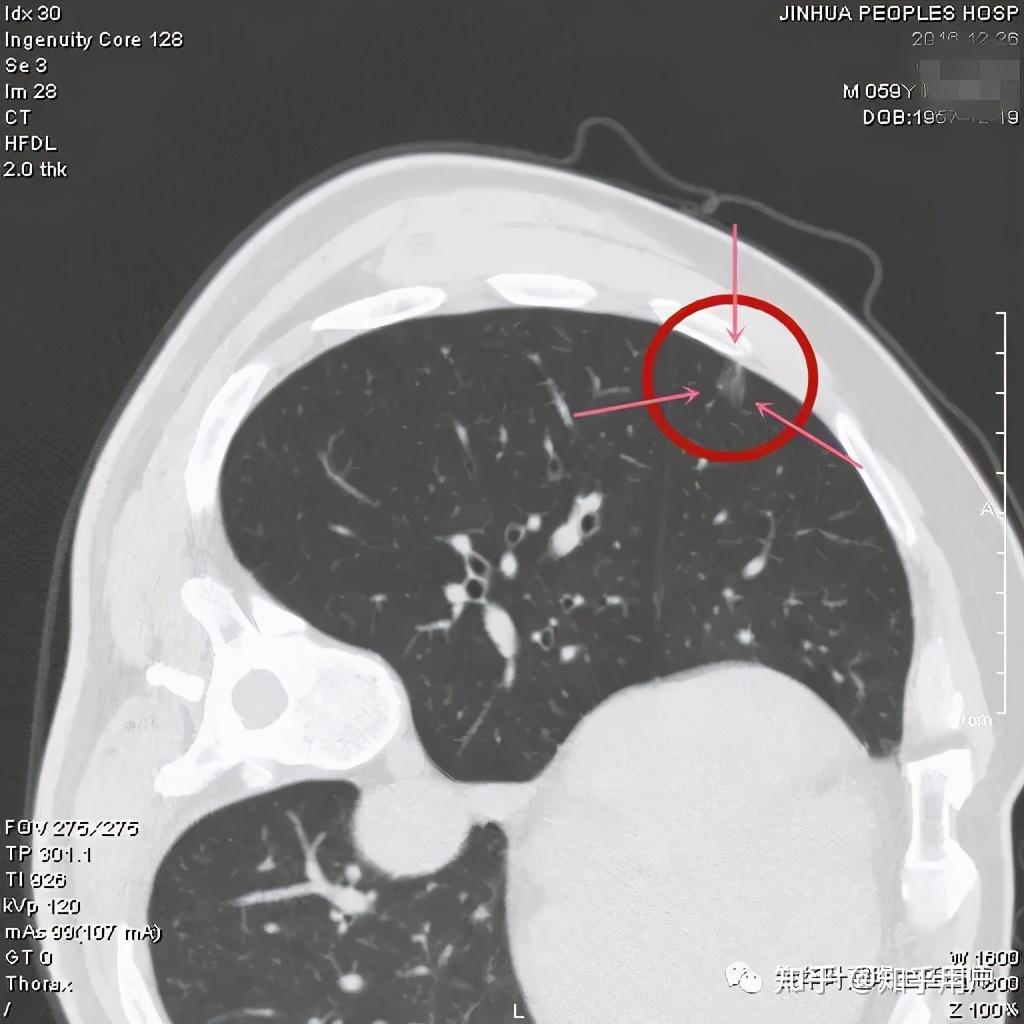

看着,非常不错,以后原位腺癌与非典型增生不是癌了,不需要手术了,至少不能按恶性肿瘤的方式进行手术了。这是好事!但真的到了临床上,如何把握,我看仍是前路漫漫,迷雾重重!我们先举几个例子,来看看影像上如何来区分AAH、AIS、MIA以及浸润性腺癌。下面的四幅CT图分别各是其中的一种,是我们术后有病理依据确诊的病例,你能分出哪张是哪种吗?

有没有高手能分辨出来?我是一头雾水,根本分不清到底哪个是哪种。都是纯磨玻璃结节,都是瘤肺边界清楚,大小都在1厘米左右或以下。现比如下面这四幅CT图也是分别为AAH、AIS、MIA以及浸润性腺癌(贴壁型),你能分得清楚哪幅图是哪种吗?

这几乎就是四胞胎,长的没什么区别,但病理类型天差地别。现在把AAH与AIS剔除出恶性肿瘤后,更是差别巨大了,是癌与非癌的区别了,但没有手术切除病检的情况下,你如何来区分?